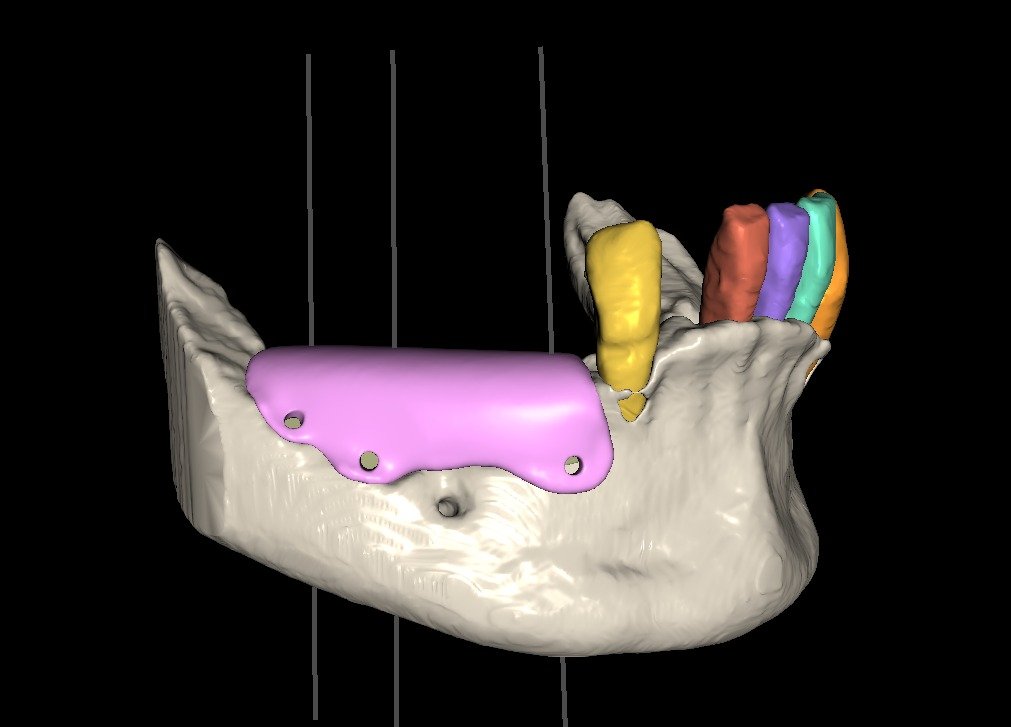

• Introducción al flujo digital en ROG.

• Integración de archivos DICOM, STL y PLY.

• Software utilizados en el protocolo:

• BlueSkyPlan: diagnóstico, segmentación y análisis del defecto.

• Exoplan / Exocad: diseño digital aplicado a la regeneración.

• Meshmixer: ajustes, correcciones y optimización del diseño.

• Segmentación ósea y dental.

• Generación del defecto virtual.

• Control tridimensional del volumen a regenerar.

• Ventajas del diseño realizado por el propio cirujano.

• Concepto de barrera personalizada.

• Principios de diseño biomecánico.

• Espesor, extensión y bordes de la barrera.

• Diseño pasivo y adaptación milimétrica.

• Planificación de tornillos de fijación:

• Número

• Posición

• Angulación

• Relación barrera hueso – tejidos blandos.

• Errores de diseño más frecuentes y cómo evitarlos.